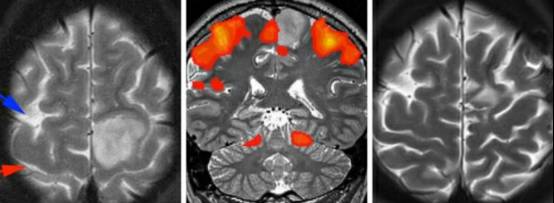

图2. 紧靠运动区前方的肿瘤需要使用运动功能区定位,确保肿瘤最大程度的安全切除。额上沟(蓝色箭头),中央沟(红色箭头)(左图)。fMRI提示位于中央小叶前部和内侧的肿瘤(中图)。术后MRI显示占位病变全切(右图)。该患者术后出现暂时性足部无力,4周后完全缓解。发生任何永久性的神经功能障碍都会削弱或消除由手术切除肿瘤带来的任何生存优势。由于肿瘤直接浸润运动功能区,有必要使用唤醒型功能区定位,术中定期检查,确保和判断肿瘤安全切除的范围。

图1. 中央沟的影像学标志。源自于额上沟(绿色箭头)水平部末端向后的第二条垂直脑沟的是中央沟(红色箭头)(左图)。更多可靠的定位方法如下:先在正中矢状位MRI找到扣带沟(绿色箭头),然后向上(边缘沟)直至大脑边缘。边缘沟位于Rolandic区(中央小叶:红色箭头包绕区)后方,(右图)。